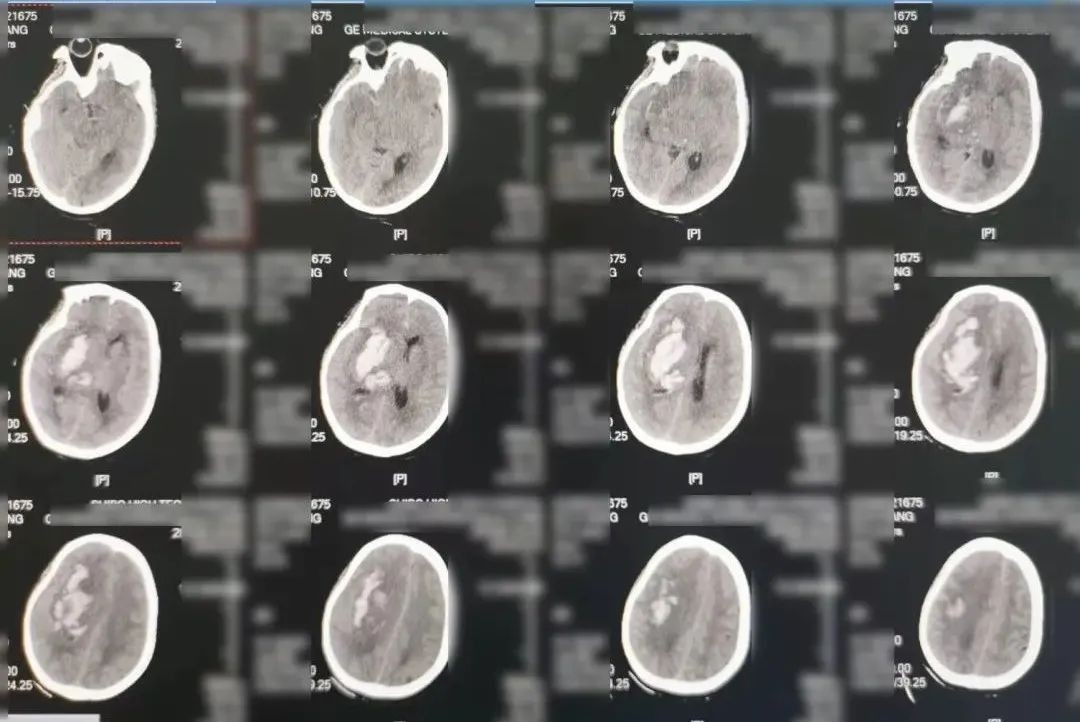

术前检查

认真分析影像学资料、快速制定手术方案,短短半小时,紧凑精心的术前准备工作便已完成。